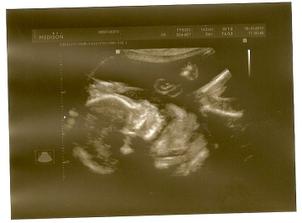

Pořídíme Míše Ríšu 🙂

tak se nám zadařilo počít sourozence, opět to byl fofr, první měsíc, takže opět trochu šok i když příjemný

zatím všechno vypadá krásně, mamince je dobře, doktoři jí hlídají na všech frontách, tak snad se nám tentokrát podaří dočkat se termínu 22.2.2011 🙂